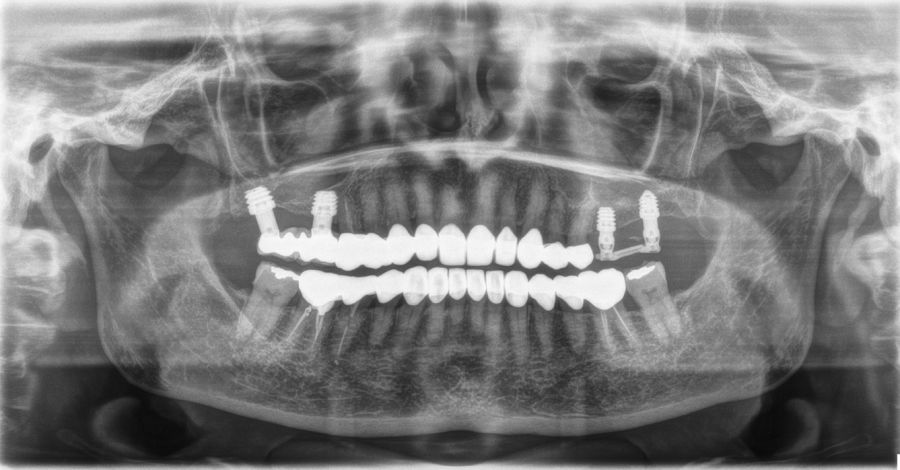

Fueron reclutados 13 pacientes que cumplieron los criterios de inclusión en los que se insertaron 30 implantes. La edad media fue de 70 +/- 1 años en el momento de la cirugía y 10 de los pacientes fueron hombres. El tiempo medio de seguimiento desde la carga fue de 126 meses (+/- 1,79; Rango 120- 150 meses). Los diámetros, longitudes y posiciones de los implantes se muestran en la Figura 4. La altura media de la cresta residual fue de 4,86 mm (+/-0,97; rango 1,95-5,88 mm). El torque de inserción medio de los implantes fue de 26,45 Ncm (+/- 1,89). Una vez insertados y cargados los implantes, la altura media final fue de 9,68 mm (+/- 2,66; rango 6,74-13,11 mm), lo que supone una ganancia promedio de 5 mm. A los 10 años, se observa una disminución media de la altura ósea ganada en los implantes en conjunto de 0, 29 mm (+/- 0,77).

La media de la pérdida ósea mesial fue de 0,73 mm (+/- 0,75 mm) y la media de la pérdida ósea distal fue de 0,98 mm (+/- 1,2 mm). No existió ningún fracaso en los implantes estudiados, por lo que la supervivencia fue del 100%. Todas las prótesis se rehabilitaron de forma atornillada mediante transepitelial, siendo un 85% de ellas puentes de 2 a 4 unidades y el resto prótesis completas. No se produjeron complicaciones en la técnica quirúrgica en ninguno de los casos estudiados, sin producirse ninguna perforación de la membrana de Schneider.

En las Figuras 5-16 se muestra uno de los casos incluidos en el estudio.

En los diferentes estudios en los que se han empleado implantes cortos en conjunción con la técnica de elevación de seno transcrestal sin colocación de material de relleno en el seno, se ha reportado una ganancia ósea de entre 1,8 y 4 mm24-27. Por esta variabilidad, la realización de este tipo de técnicas sin injerto añadido suscita cierta controversia. En algunos estudios la ganancia ósea inicial decrece desde 1,8 mm hasta 1,3 mm o 1,1 mm al transcurrir uno y tres años respectivamente8. Otros estudios en cambio obtienen resultados similares a los de este trabajo con ganancias endosinusales de 3,9 +/- 1,0 mm tras un año y 4,1 +/- 1,0 mm tras tres años de seguimiento24-27. En los diferentes estudios que utilizan abordajes transcrestales, existen diferentes técnicas, con diferentes implantes (superficies, morfologías) y distintos métodos de fresado. Esto puede ser, bajo nuestro punto de vista lo que marca la diferencia entre unos datos de supervivencia y otros, o incluso los malos resultados en crestas con volumen óseo residual que recomiendan no realizar este procedimiento en estos casos extremos. En nuestra serie de casos, la ganancia promedio en altura sobre el ápice ha sido de 5 mm, existiendo un rango de 6,74-13,11 mm. Estos datos son ligeramente superiores a los encontrados en la literatura internacional y, además se mantienen durante el periodo de seguimiento, hasta 10 años después de la cirugía, donde la media de reabsorción del volumen ganado se situó en 0,29 mm, por lo que se puede decir que la técnica mostrada es predecible en el tiempo.